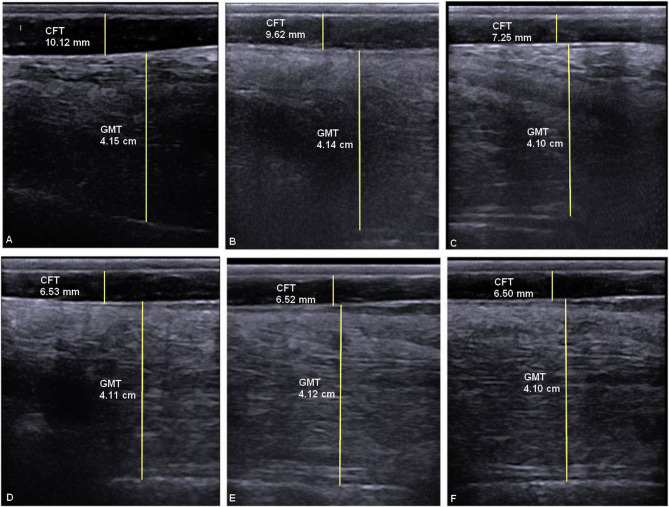

Results: On six occasions, the following were evaluated: body weight (BW), body condition score (BCS), ultrasound subcutaneous CFT, ultrasound gluteal muscle thickness, liver ultrasonography, and blood metabolites. The ultrasound CFT was significantly reduced at 4 days of fasting (P < 0.05). Donkeys with ≥ 7 mm of CFT before fasting were 6 times more likely to develop hyperlipidemia post-fasting (P < 0.01). Hepatic ultrasonography showed no hepatomegaly. Decrements of the portal vein (PV) diameter were noticed during fasting. The hepatic relative echogenicity (RE) significantly increased after 4 days of fasting, and then decreased after fasting (P < 0.05). The RE of ≥ 78 is a critical threshold for diagnosing hyperlipidemia (P < 0.001). The serum concentrations of triglycerides, total cholesterol, very low-density lipoproteins, high-density lipoproteins, and low-density lipoproteins peaked at 4 days of fasting (P < 0.05). The serum concentrations of FFA increased during fasting (P < 0.05) and then dropped after fasting.